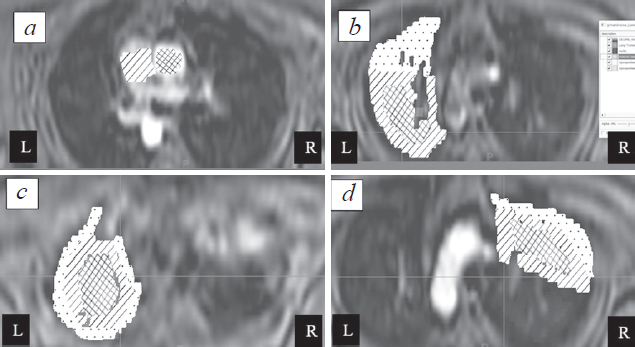

The analysis was performed for the corresponding ROIs which were selected in two planes (Figs. 1, 2). The ROI was chosen while considering the blood supply to the apexes of the lungs, whereas segments of the apexes of the lungs were considered with a separate study of the central and peripheral zones.

Fig. 1. Axial reconstructions of image with dynamic contrast enhancement. а – Selection of ROI in the area of the pulmonary trunk and ascending aorta for a qualitative assessment of the suitability of the data; b, c – Selection of areas of interest in the left lung: peripheral and central sections of the apical-posterior segment of the left lung at different levels are demonstrated; d – the same for the right lung with separate examination in the upper lobe of the apical and posterior segments. These are mirror images of classic-oriented CT/MRI projections

Рис. 1. Аксиальные реконструкции серий изображений с динамическим контрастным усилением. а — Выбор ROI в области легочного ствола и восходящего отдела аорты для качественной оценки пригодности данных; b, c — выбор зон интереса в левом легком: продемонстрированы периферические и центральные отделы верхушечно-заднего сегмента левого легкого на разных уровнях; d — то же для правого легкого с отдельным рассмотрением в верхней доле верхушечного и заднего сегментов. Следует обратить внимание, что данные изображения являются зеркально отраженными относительно классической ориентации компьютерных и магнитно-резонансных изображений

First, the level of the pulmonary trunk and ascending aorta was examined to assess the reference function (Fig. 1, a, b). The criterion for selecting images was the absence of a peak in the curves of the dependence of the signal intensity on time, for example, in cases of earlier contrast enhancement or manifestation of individual physiological characteristics. Similarly, data obtained from four participants were excluded, and data of 10 volunteers were recognized as suitable for further analysis (14 volunteers examined in total).

Further, the zones of interest were selected in the apical segments from the level of the aortic arch and above with an interval of 1.5–2 cm, depending on the anthropometric parameters of the patient. In total, four levels were assessed, namely, the first at the level of the aortic arch, the last at the apex of the lung, without isolating the peripheral section.